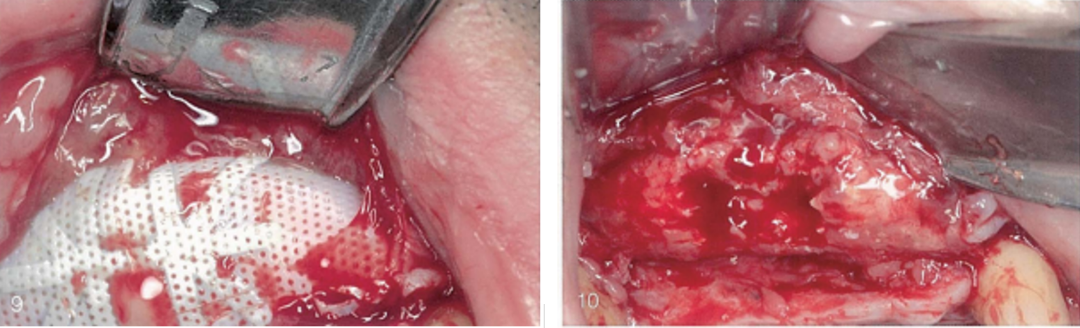

(9)唇侧观,翻瓣后可见屏障膜。

(10)唇侧观,取出屏障膜后的术区。可见感染的移植材料表层松软。